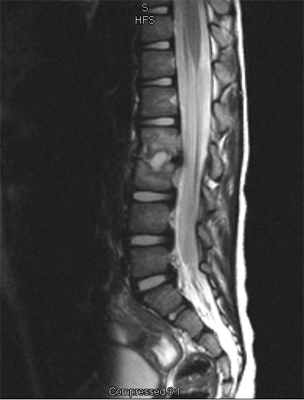

An MRI may be required if further examination of the spine is needed. An MRI machine uses magnetic waves, not X-rays, to show the soft tissues of the body. These tissues include the spinal cord, nerves, and discs. It can also evaluate spinal bones. An MRI allows your healthcare professional to look at slices of the area in question. The test may require the use of dye in an IV. Sedation or anesthesia may be needed to help your child lie still for this test.

A computed tomography (CT) scan may also be ordered. This test is best for evaluating problems with the vertebral bones. Children usually tolerate this test well, however, this test exposes them to radiation, which is significantly higher than during plain x-rays. Sometimes this test may require dye in the spinal canal fluid for easier identification of the spinal cord and nerve root anatomy. When dye is injected for this purpose, the technique is called a myelogram.

In the early stage of the injury an X-ray may not show a fracture. Special imaging tests such as magnetic resonance imaging (MRI), computed tomography scans (CT), or a bone scan may show signs of a stress fracture. Spondylolysis may cause pain in a particular spot in the low back and spasm of the muscles along the spine. Often it will cause pain into the buttocks or thighs. Spondylolysis will often heal with the appropriate rest, a change in activity levels, and by avoiding hyperextension and rotation of the spine. Bracing may be helpful if symptoms do not get better.

X-rays are recommended for most children complaining of back pain due to the fragile nature of their developing spine. Views of the spine from the front, the side, and part way in between (oblique) should be taken. X-rays will allow examination of bone as well as the disc spaces.